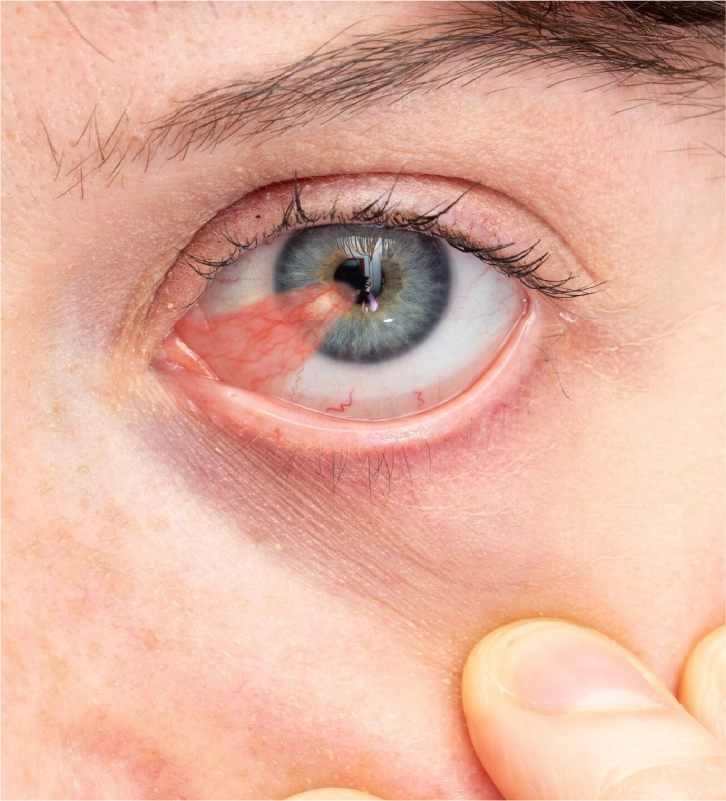

CIRUGÍA DE PTERIGIÓN

CIRUGÍA DE PTERIGIÓN

La cirugía de pterigion es ambulatoria, indolora y se realiza bajo anestesia local.